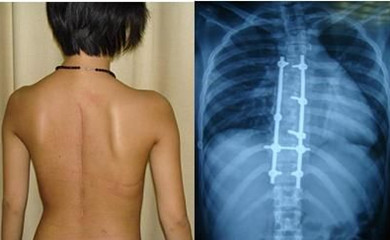

4、手术治疗:对脊椎严重变形的病人,可以采取手术的方法治疗强直性脊柱炎,髋关节严重受损病人可行关节修补或置换术。